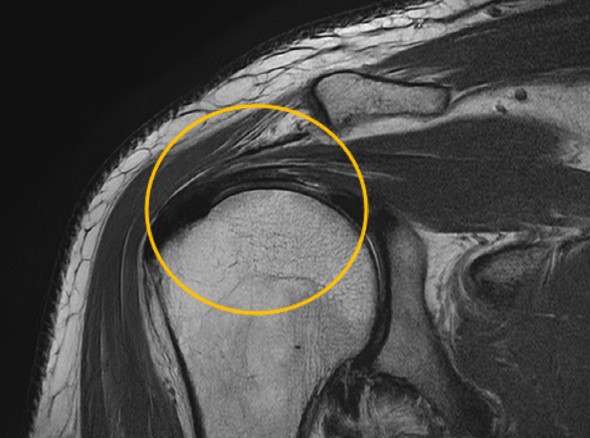

어깨충돌증후군이 발생하게 되면 회전근개에 염증이 발생하게 되고

급성 부종을 일으키게 됩니다.

30대를 시작으로 50대까지 증상이 지속적으로 악화되고 통증도 점차 커집니다.

증상이 심한 경우 일상 생활에 어려움이 발생되어 수술적인 치료를 고려할 수 있습니다.